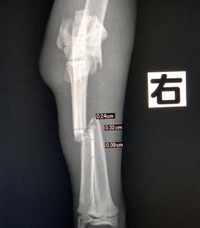

ゴミ捨て場で「ギャー」という子猫の悲鳴→4本足が折れていた 獣医師「限りなく虐待に近い骨折」、その後は?

【写真】歩けるようになった子猫

【写真】手術後の子猫